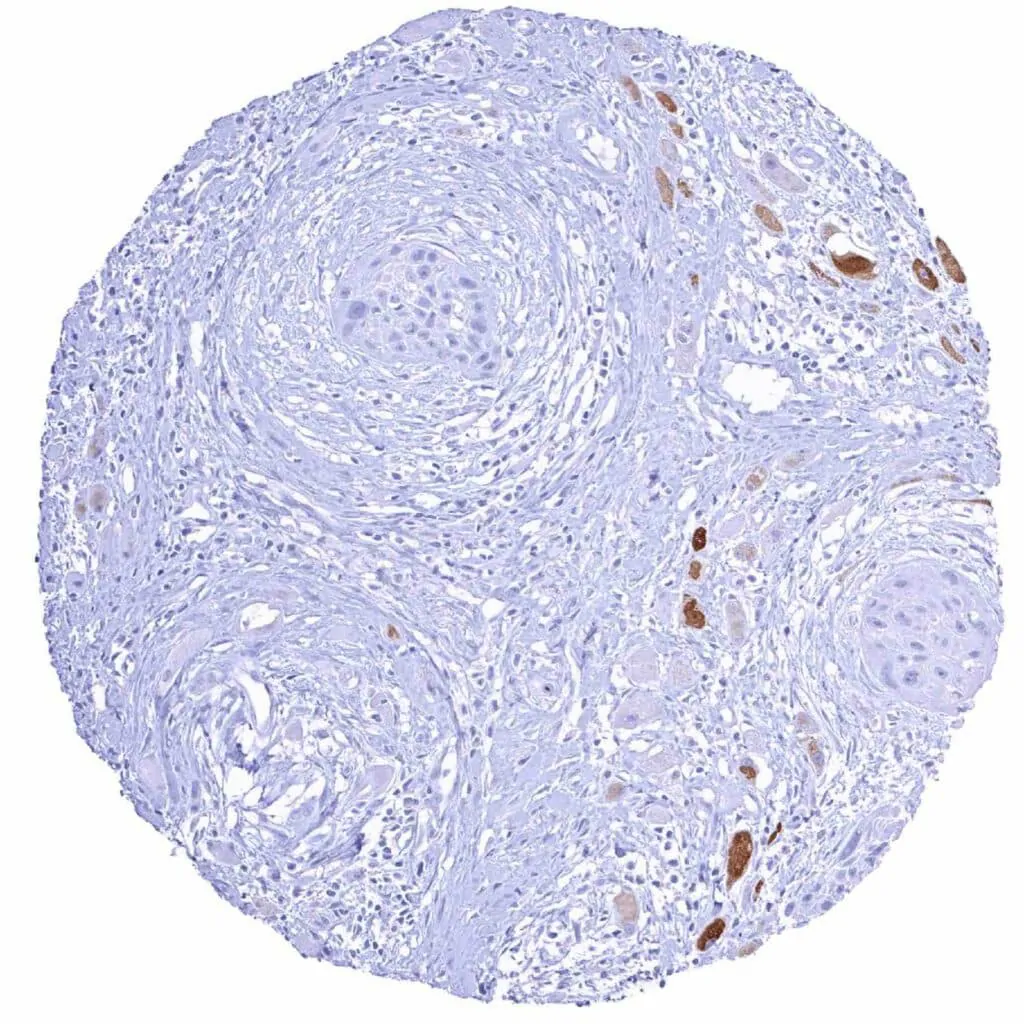

Oral cavity – MYH7 negative squamous cell carcinoma showing infiltration of degenerated MYH7 positive skeletal muscle fibres